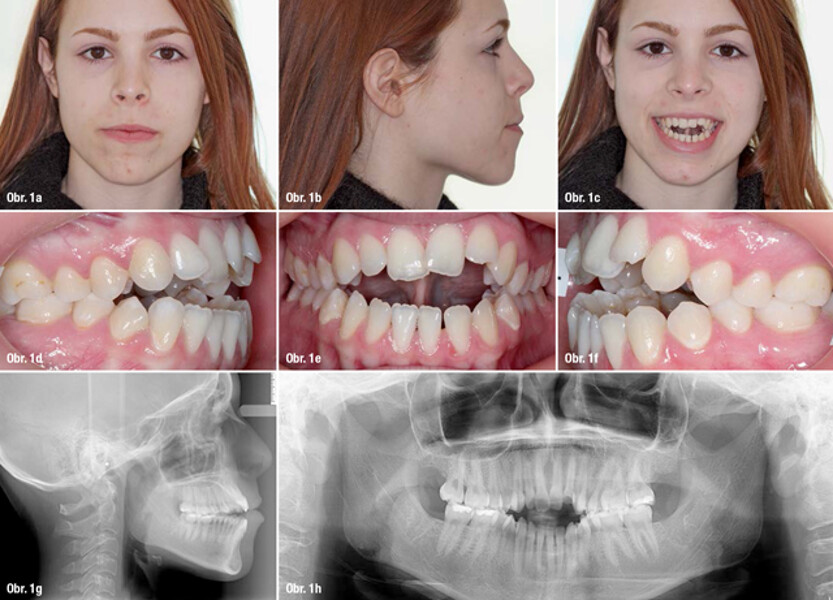

„Sagittal First“